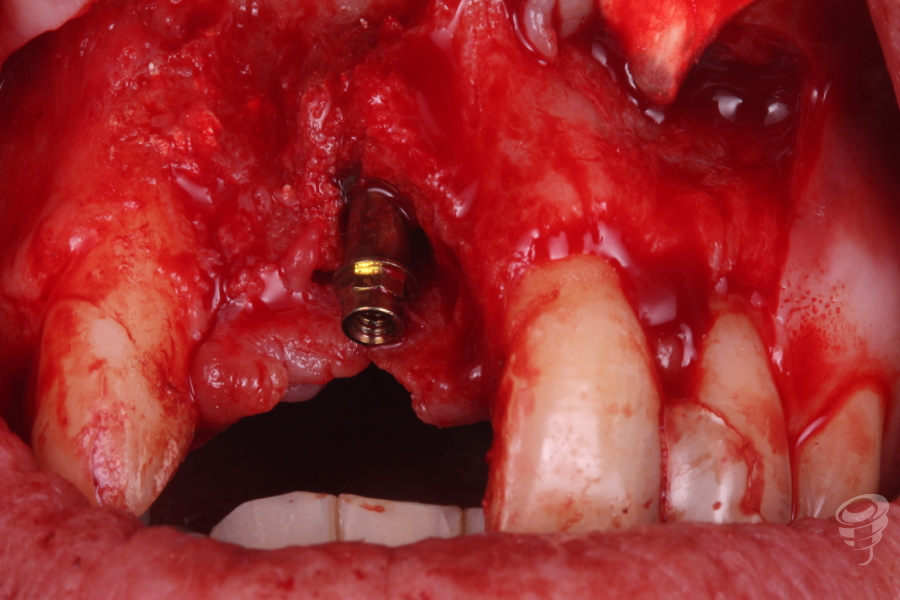

- Realizamos la explantación del implante colocado en una posición anómala con un extractor de implantes Galimplant de una manera muy simple, ya que no estaba totalmente osteointegrado.

- Posteriormente empezamos a realizar la preparación del lecho óseo con el protocolo de fresado Galimplant y colocar un nuevo implante IPX 4012 en la zona del 11.

Una vez colocado, insertamos un pilar multi-posición recto estético anti-rotatorio de 3mm.

Imagen 4